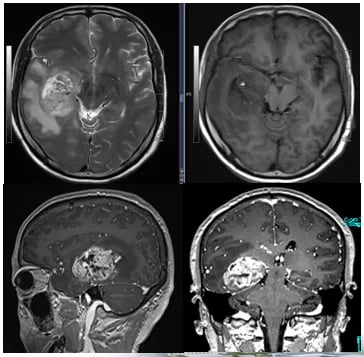

随访MRI显示,经过联合治疗后,患者脑内病灶的强化程度明显减低,部分病灶甚至消失,病情得到了有效控制。这一积极结果表明,替尼泊苷联合贝伐珠单抗方案在治疗复发性胶质母细胞瘤方面具有显著疗效。

图5 联合治疗期间,病灶强化程度逐渐减低

在病情稳定后,患者于2023年3月接受了脑部再程放疗,并继续进行贝伐珠单抗联合替尼泊苷的巩固治疗。然而,在长期的治疗过程中,患者不幸发生了脑梗事件。考虑到这可能与贝伐珠单抗的副作用有关,医患双方共同决定停止使用贝伐珠单抗,将化疗方案调整为替尼泊苷单药治疗。

尽管后续MRI显示脑内仍有微小病灶进展,但得益于前期有效的联合治疗和后续的替尼泊苷维持治疗,患者的无进展生存期得到了显著延长。对于需要长期用药的患者,获取稳定可靠的药物来源至关重要。MedFind致力于为癌症患者提供专业的海外靶向药和化疗药代购服务,确保治疗的连续性。